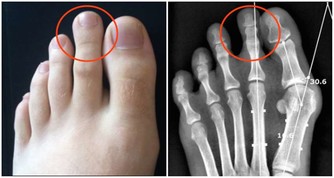

3、大腳趾外側磨損

大腳趾外側磨損多由於拇外翻造成,即大腳趾和足部相連處的關節傾斜超過15度所致。走路時,這些患者會傾向於腳跟過早抬起,將過多的壓力施加給大腳趾。

【點評】大腳趾外翻一般是先天造成的,但是也可能由於久坐,經常穿高跟鞋等導致腳尖長期朝下伸展造成的。大腳趾外翻不但會誘發雞眼等疾病,也不利於足部骨骼健康,這類人群儘量少穿鞋面過窄、鞋跟過高的鞋子,平時要經常活動腳踝,放鬆腳後跟。